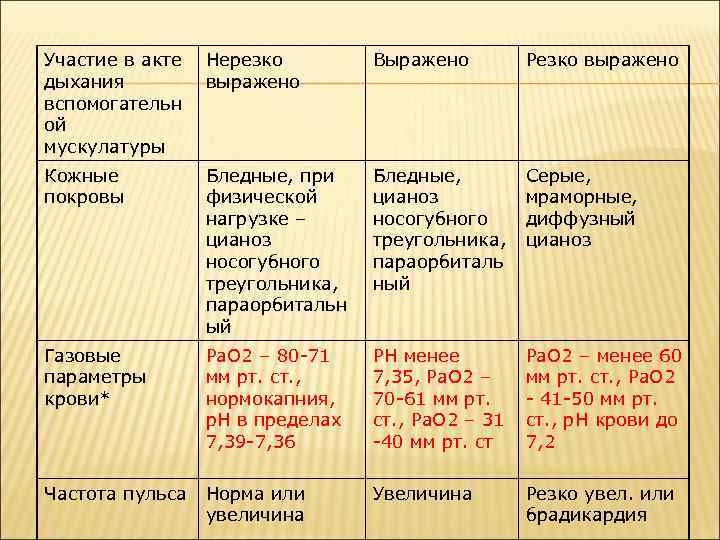

Участие в акте дыхания вспомогательн ой мускулатуры Нерезко выражено Выражено Резко выражено Кожные покровы Бледные, при физической нагрузке – цианоз носогубного треугольника, параорбитальн ый Бледные, цианоз носогубного треугольника, параорбиталь ный Серые, мраморные, диффузный цианоз Газовые параметры крови* Ра. О 2 – 80 -71 мм рт. ст. , нормокапния, р. Н в пределах 7, 39 -7, 36 РН менее 7, 35, Ра. О 2 – 70 -61 мм рт. ст. , Ра. О 2 – 31 -40 мм рт. ст Ра. О 2 – менее 60 мм рт. ст. , Ра. О 2 - 41 -50 мм рт. ст. , р. Н крови до 7, 2 Частота пульса Норма или увеличина Увеличина Резко увел. или брадикардия